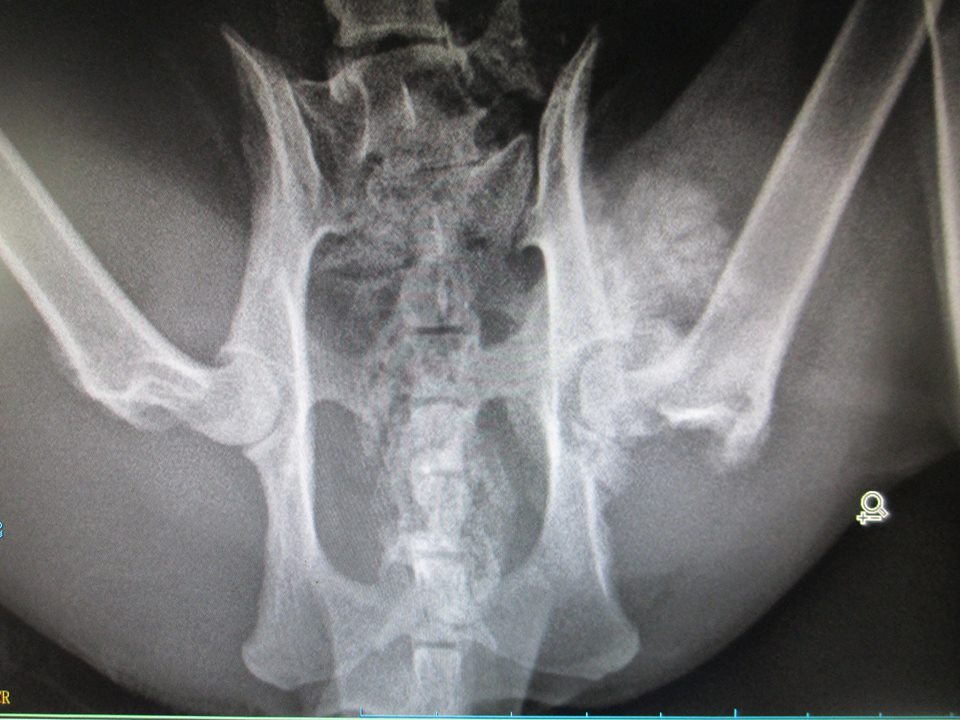

主題: 寒冬中的斷尾骨折小花 申請者姓名: 吳佩君 花色: 申請日期: 2014-03-17 13:30:01 申請者部落格: 申請者臉書網址: 所在縣市/合作醫院: 台北市/欣旺動物醫院 治療費用: 9800元 需求人數: 12人 已結案 (2014-05-18 09:40:36) 報名人員: Sunny Chen(已付款)、Forest(已付款)、grace0710(已付款)、megumi(已付款)、ERic YU(已付款)、Parry Hsu(已付款)、Queenie Chang(已付款)、clement(已付款)、豆腐人 x3(已付款)、小四(已付款)、 候補人員: 動物病情說明: 過年,對於我們是個喜慶的節日,對於斷尾的小花......卻沒有絲毫的歡喜

寒冬中忍受的斷尾骨折的疼痛,卑微的街貓們只能在人類的夾縫中生存,偏偏小花承受著不知是野狗咬傷或是街貓打架到潰爛見骨的疼痛與可能骨折的後腿,行動是如此的緩慢與笨拙,想見這過年他該如何躲避無情的鞭炮與飢餓??

或許是過度的驚嚇,可能是身體的痛楚,小花在誘捕籠中沒有一點掙扎與反抗,而是一種接受命運淬鍊的無奈與冷靜,也或許是身體的疼痛已經讓他沒有力氣反抗了。過年假期,中和地區的醫院並沒有營業,只得送往松山的欣旺動物醫院。空氣中濕潤的微雨更諷刺著年節的氣氛。小花終於見到了活下去的希望。

醫生稍事檢查,只能確定優先處理斷尾的傷口,視情況治療後腿(骨折OR拉傷),而且小花並未剪耳,所以節紮是勢在必行的了。